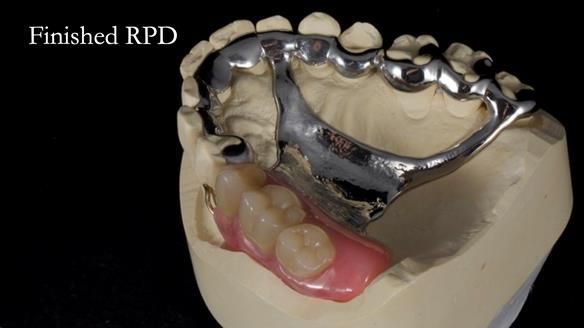

Welcome to Newsletter 64. I'll walk you through the process of providing a Mk 2 metal-based partial denture (RPD), for Ian a retired Veterinary Surgeon aged 78. The RPD was made at an increased vertical dimension and acted as an occlusal stabilisation splint - reducing the wear and bite force on the remaining natural teeth.